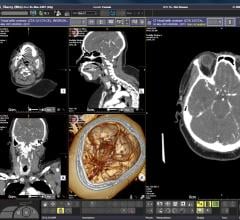

Vital Images, Inc., a Minneapolis-based advanced medical imaging and informatics company, launched “VNA on demand” to the global marketplace. While Vital continues to lead the world in advanced visualization and personalized medicine algorithms, 2016 heralds an increased focus on enterprise informatics.